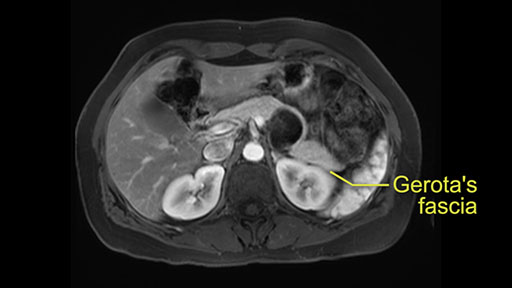

Posterior pancreas margin: Gerota's fascia

In terms of maintenance of the regular planes, other factors that we need to consider is whether you need to enter in posteriorly to Gerota’s fascia to obtain an adequate margin and anteriorly to ensure the tumor can be mobilized safely off of the posterior wall of the stomach.

So first step that we do: mobilize the splenic flexure first to visualize Gerota’s fascia and that would help bring down the colon and expose the pancreatic tail. So now that the pancreas is visible, division of the gastrocolic ligament will come into view. And a window can be created at the inferior edge of the pancreas to slowly lift the inferior edge to expose the splenic vein behind. This is the slow-down moment that I am talking about because the MR shows that there could be contact with the cyst. It’s important to know that to avoid perforation, to avoid rupture of the cyst, because we need to avoid touching the cyst, it is quite a size of 4.3 about 4cm.

After you've slung the pancreas, to the left of the cyst, and if you encounter any adrenal involvement later after you have transected the pancreas and you move to the left side of the patient towards the spleen, take either the entire or partial left adrenal gland with the resection. If you go underneath the adrenal gland, and it's probably best to do a full RAMPS (Radical Antegrade Modular Pancreatosplenectomy) procedure, that is where you take the Gerota’s fascia completely onto the mucinous cyst. And that's very crucial to get a radical resection if you think the adrenal gland is involved.

So at the beginning of the operation, after you’ve placed the trocars, mobilization of the pancreas, starting with the posterior mobilization of the entire pancreas. And then you can do it several ways. The way I personally prefer is to go underneath the pancreas. So you can sling it, you can hang it with a vessel loop. Now, there are two ways to do that. For a cancer, which this is not, but for a cancer, you would incise Gerota’s fascia and go underneath. So you would take Gerota’s fascia always with the specimen. You can have a debate on whether you should do that here as well. But I think strictly speaking, it's not necessary.